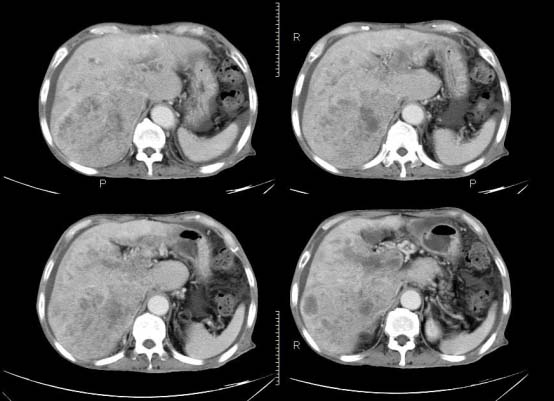

以下是引用杀毒软件在2010-3-30 18:11:00的发言:[br]考虑---hcc侵犯侵犯周围组织〔胰腺、胆管、肠系膜上动静脉〕伴门脉、下腔静脉癌栓形成、动-静脉瘘、肝门、腹腔动脉周围淋巴结转移可能性大、腹水。

以下是引用pujunzhi在2010-3-31 8:45:00的发言:[br]支持 肝癌并多发肝内转移,胰头、肝门、腹腔动脉周围淋巴结转移,下腔静脉癌栓形成,肝硬化、腹水。

以下是引用jsgdoctor在2010-3-30 20:42:00的发言:[br]考虑---hcc侵犯侵犯周围组织〔胰腺、胆管、肠系膜上动静脉〕伴门脉、下腔静脉癌栓形成、动-静脉瘘、肝门、腹腔动脉周围淋巴结转移可能性大、腹水。